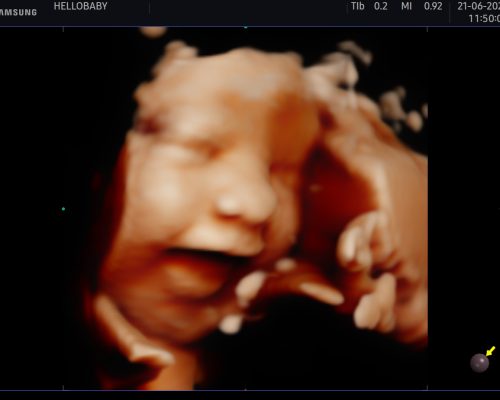

La ecografía 5D y realidad es una técnica avanzada de imágenes médicas que utiliza ultrasonidos para explorar el interior del cuerpo, en este caso, el útero materno. Lo que hace que la ecografía 5D se destaque es su capacidad para proporcionar imágenes de alta definición y en tiempo real del feto en desarrollo. A diferencia de las ecografías tradicionales, que ofrecen imágenes bidimensionales (2D) o tridimensionales (3D), la ecografía 5D brinda una experiencia casi tridimensional con una profundidad y claridad notables.

La pregunta más común es cuándo es el mejor momento para someterse a una ecografía 5D. Aunque es posible realizar una ecografía 5D en diferentes etapas del embarazo, el período más recomendado para obtener las imágenes más nítidas suele ser entre las semanas 26 y 32 de gestación. Durante este período, el bebé ha crecido lo suficiente como para que los rasgos faciales y los movimientos sean claramente visibles. Sin embargo, es importante tener en cuenta que cada embarazo es único, y la calidad de las imágenes puede variar según varios factores, como la posición del bebé y la cantidad de líquido amniótico.